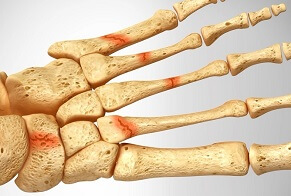

Joint inflammation from build-up of uric acid crystals - common causes of foot pain

Causes: Diet, medication, genetics, medical conditions, obesity

Symptoms: Intense pain, swelling and redness. Lasts 5-10 days and often recurs

Full Article: Foot Gout